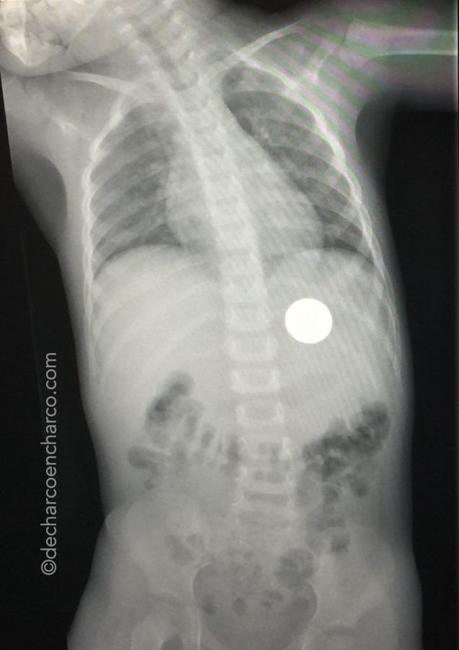

Tanto si lo ha expulsado como si no hay que llevarle a urgencias, especialmente si el objeto puede pinchar o cortar. Si lo ha expulsado viene bien ver si ha hecho algún daño en la garganta. Si no lo ha expulsado, para ver dónde está a través de una radiografía. Lo malo de la radiografía es que los objetos metálicos como las monedas se ven perfectamente, pero los de plástico no.

En el hospital nos dirán cómo proceder. En caso de que el objeto esté en el estómago habrá que esperar a que el niño lo eche con las heces de forma natural. Lo normal es que en ese tiempo antes de echarlo el niño no tenga síntomas ni molestias, quizás algún malestar cuando el objeto sale del estómago, ya que el canal por donde tiene que pasar se estrecha. Si hay una obstrucción, habrá que sacar la moneda de forma "artificial": sedando al niño para sacarla por la boca con un endoscopio.

Si a los 7 días no lo ha echado, volveremos a hacer una radiografía para ver dónde está.